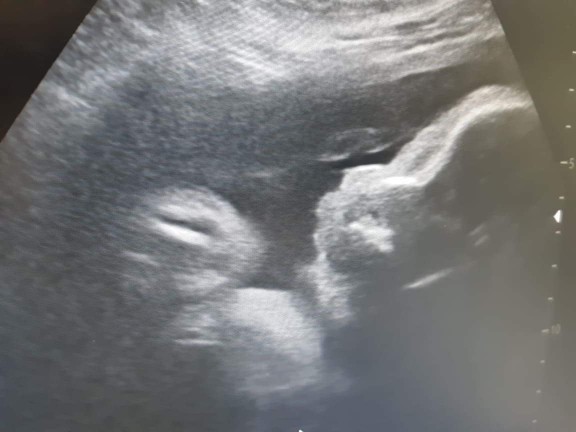

มีบ้านไหนซาวด์แล้วจมูกโด่งแบบนี้มั้ยคะ ออกมาจมูกน้องโด่งแบบนี้รึเปล่า? นี่คุณหมอบอกโด่งมาก?